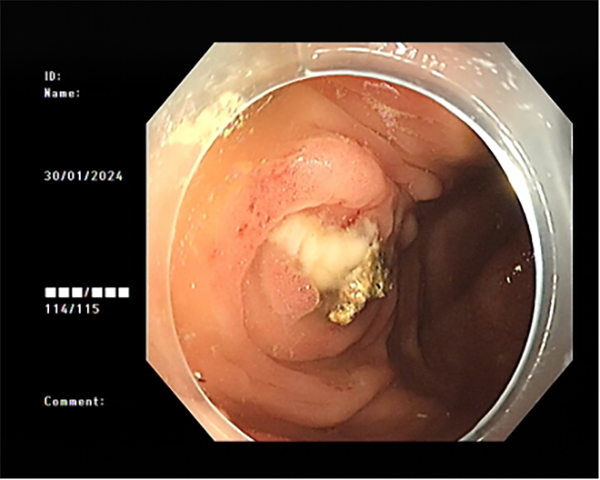

患者李某因慢性腹痛、腹瀉來消化內(nei)科(ke)就診,在(zai)腸鏡檢(jian)查過(guo)程(cheng)中(zhong)髮(fa)現(xian)患者闌尾開口處明顯腫脹、充血,并有(yǒu)白色膿液排(pai)出,進(jin)一(yi)步完善(shan)腹部(bu)CT後(hou)明确診斷(duan)闌尾炎、闌尾糞石嵌頓。征得患者同意後(hou),在(zai)邸雅南(nan)主(zhu)任的(de)帶領(ling)下,張波(bo)副主(zhu)任咊(he)康奎、青勝(sheng)醫(yī)生(sheng)等(deng)團(tuán)隊(duì)成(cheng)員(yuan)通(tong)過(guo)腸鏡活檢(jian)孔道送入“洞察”子(zi)鏡(經(jing)口膽道鏡)進(jin)入闌尾腔,清(qing)晰觀察見到(dao)闌尾腔粘膜明顯充血、糜爛,并見大(da)量膿液,闌尾中(zhong)段狹窄,擴張狹窄後(hou)膽道鏡越過(guo)狹窄段到(dao)達闌尾底部(bu),見一(yi)塊狀黃色闌尾糞石,應用(yong)取石網籃成(cheng)功取出糞石,并将闌尾腔內(nei)全部(bu)糞石殘渣沖洗幹淨。術(shù)後(hou)第二日(ri)腹痛明顯緩解并出院。

闌尾開口膿性分(fēn)泌物(wù)